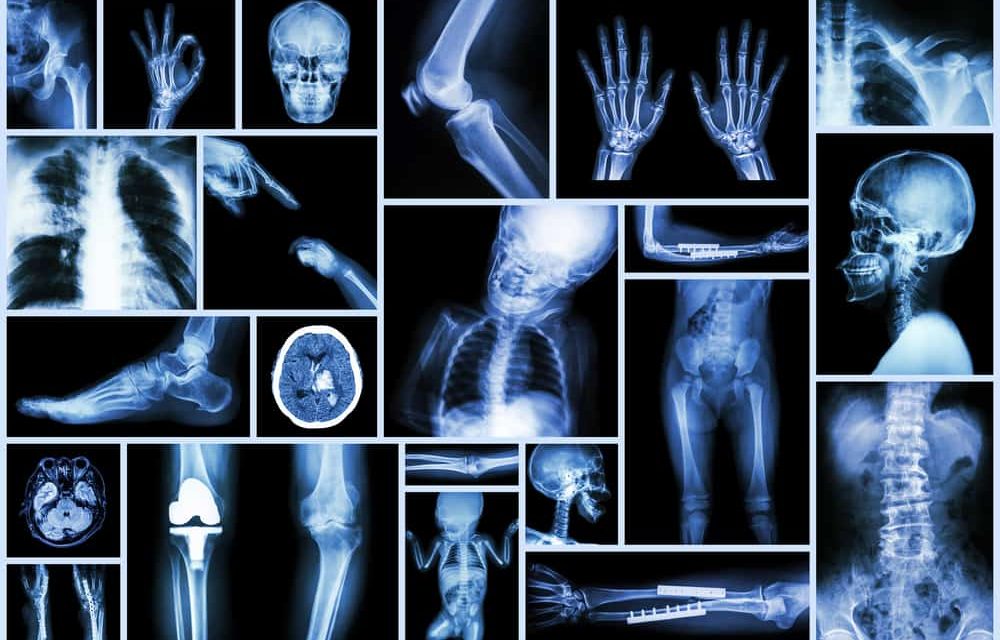

OI develops when there is a problem with the production of type I collagen. There are currently eight different types of OI defined as type 1-8. Of the 8 type I is the most common. In type I the quality of the collagen is normal, however it is not being made in sufficient quantity. This causes the bones to fracture easily, poor muscle tone and there’s also usually a blue-gray tint to the sclera. In type II the collagen is neither of sufficient quality or quantity and unfortunately most diagnosed with the type die with in the first year. Type III occurs when there is enough collagen, but it is defective. This type is also referred to as the “progressive deformity” type.

Type IV is opposite type I in that there is enough collagen but the quality is poor causing the bones to fracture easily. Type V presents with the same clinical signs as type IV, however under further examination there is a mesh-like appearance to the bone. In type V there is a hardening of the membrane between the ulna and radius, the two bones that are the forearm. Type VI also presents like type IV however when examined further the bone has a fish scale appearance. Type VII was discovered in 2006 and is a recessive type of osteogenesis imperfecta. Type VIII also recently discovered is caused by a mutation in a different gene known as LEPREI.